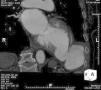

At six-month follow-up, the patient remains asymptomatic, with no adverse events, and the device is in the appropriate position confirmed by CT (Figures 3 and 4).

Figure 4.

Computed tomography angiography (axial view) showing the Amplatzer® ASD device six months after the procedure.